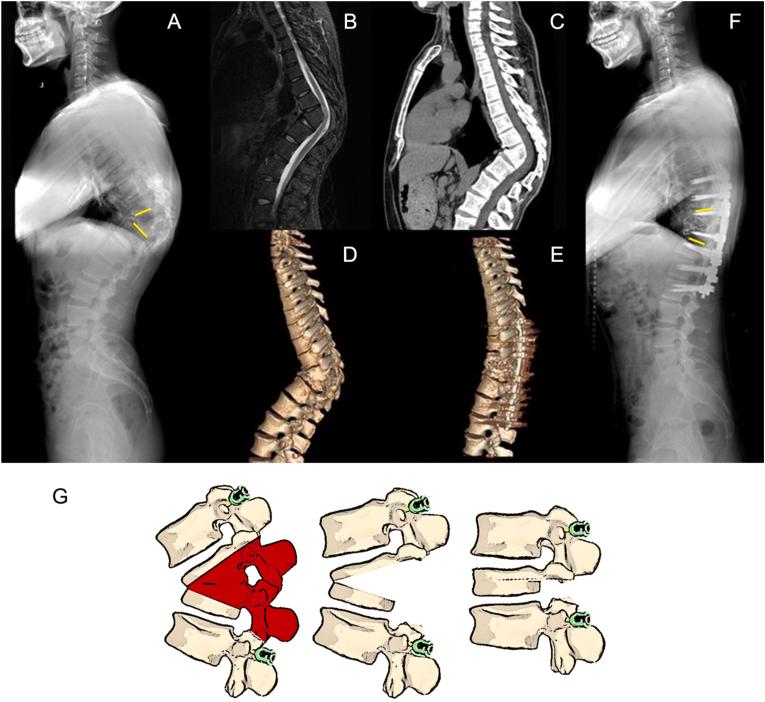

经椎间间隙后路脊柱矫正截骨手术的经椎间截骨分类

Trans-intervertebral osteotomy classification of posterior spinal corrective osteotomy procedures via the intervertebral space.

•This is a diagnostic study for a classification for posterior spinal osteotomy procedures via the intervertebral space.•Proposed ​ ​with ​ ​and ​, differ from the SRS-Schwab osteotomy classification.•Give of "" () for posterior spinal osteotomy procedures.•Thoroughly discussed about the of posterior spinal osteotomy procedures via the intervertebral space.•Systematically introduced the TIO technique with .

摘要

•这是一项关于经椎间隙后路脊柱截骨手术分类的诊断性研究。

•与SRS - 施瓦布截骨分类法不同,由[具体人员1]和[具体人员2]提出。

•给出了后路脊柱截骨手术的“[具体名称]”([具体描述])。

•深入讨论了经椎间隙后路脊柱截骨手术的[相关内容]。

•系统介绍了采用[具体技术]的TIO技术。